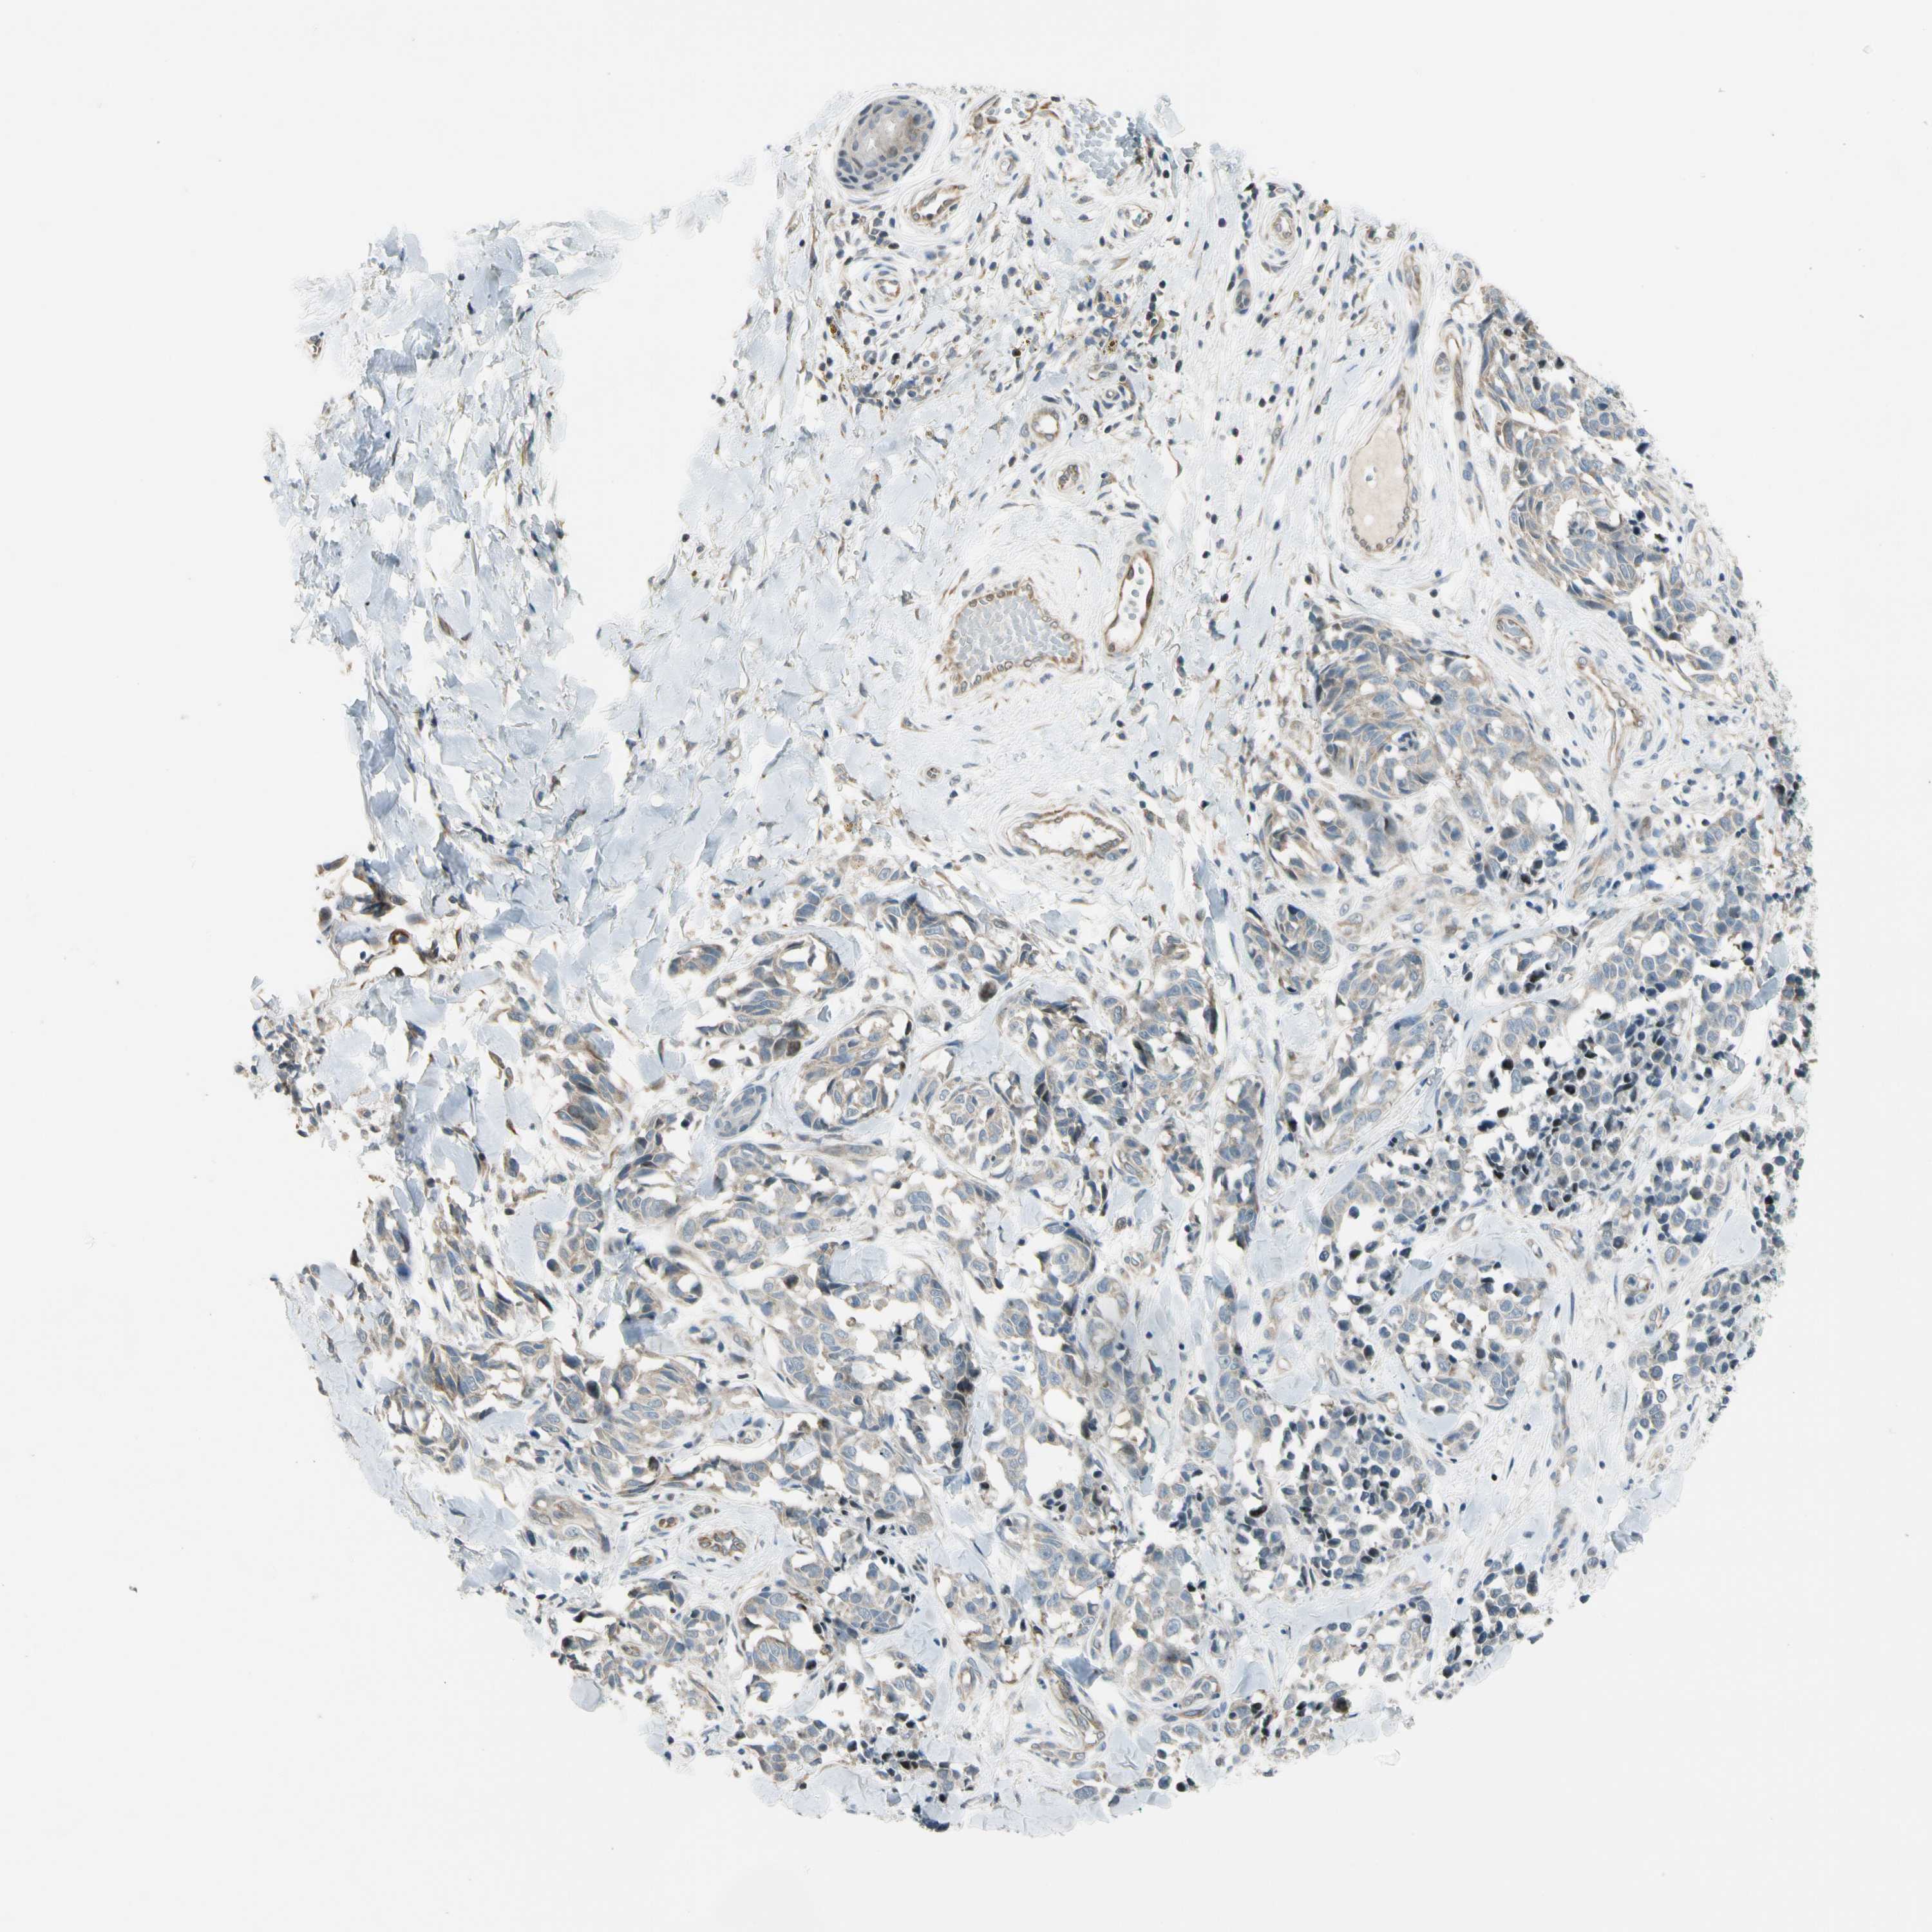

MELANOMA - Protein expressioni

A mouse-over function shows sample information and annotation data. Click on an image to view it in a full screen mode. Samples can be filtered based on level of antibody staining by selecting one or several of the following categories: high, medium, low and not detected. The assay and annotation is described here.

Note that samples used for immunohistochemistry by the Human Protein Atlas do not correspond to samples in the TCGA dataset.

Antibody stainingi

Antibody staining in the annotated cell types in the current human tissue is reported as not detected, low, medium, or high, based on conventional immunohistochemistry profiling in selected tissues. This score is based on the combination of the staining intensity and fraction of stained cells.

Each image is clickable and will lead to virtual microscopy that enables deeper exploration of all samples and also displays staining intensity scores, fraction scores and subcellular localization as well as patient and tissue information for each sample.

Antibody HPA008507

Staining

High

Medium

Low

Not detected

Intensity

Strong

Moderate

Weak

Negative

Quantity

>75%

75%-25%

<25%

None

Location

Nuclear

Cytoplasmic/membranous

Cytoplasmic/membranous,nuclear

Malignant melanoma, NOS

Malignant melanoma, Metastatic site